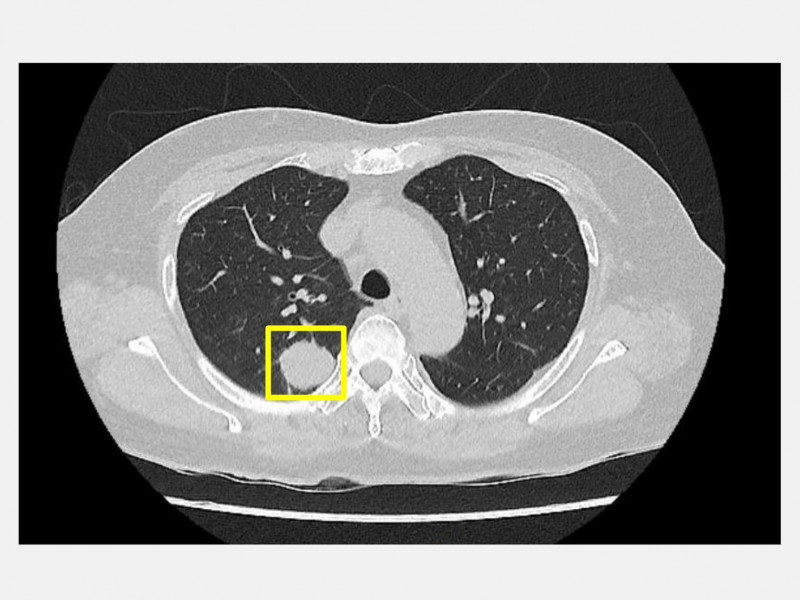

〔記者許國楨/台中報導〕沒抽菸、沒肺癌家族史,怎麼可能?台中市50歲吳先生近日得知右肺長了一顆2公分腫瘤時,難以置信,平日作息規律、自認身體健康的他,只是在例行健康檢查中做了低劑量電腦斷層(LDCT),沒想到這一檢查意外救了命。

吳先生在得知結果後,立刻前往仁愛長庚合作聯盟醫院(大里仁愛醫院)尋求協助,經胸腔暨心臟血管外科醫師林宜右詳細評估後,確診為肺部腫瘤,建議盡快手術切除,且為降低手術創傷與術後疼痛,決定採用目前最先進的「單孔達文西機器人微創手術」(健保給付)進行治療。